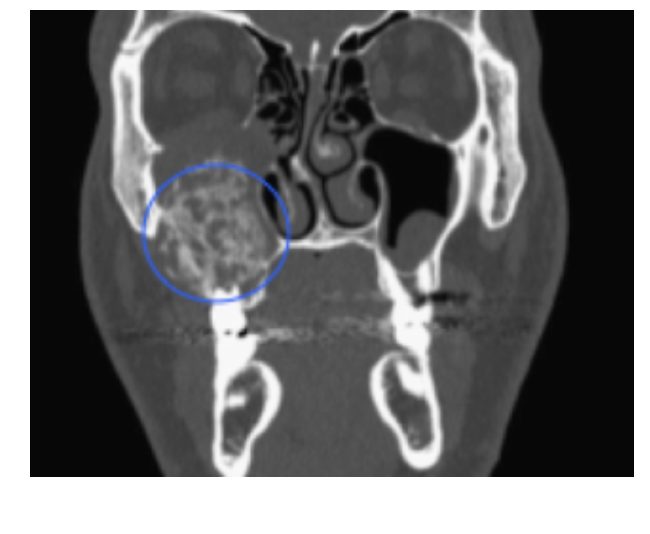

Hyperparathyroidism

A

Multiple bone lesions that look like CGCG’s

* due to Excessive PTH Levels

Brown Tumor:

* Excess osteoclast activity–> Elevated Alkaline Phosphate